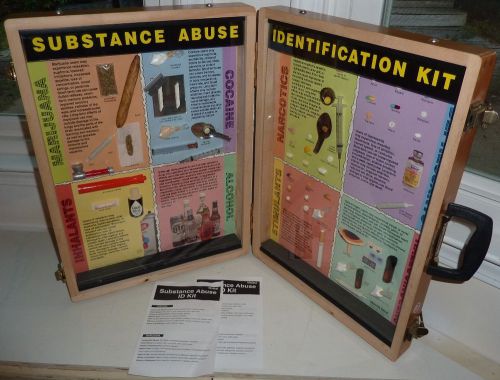

Health EDCO Substance Abuse briefcase display training kit